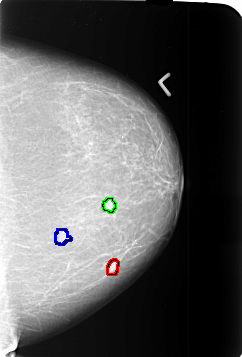

B_3371_1.RIGHT_MLO

FILE: B_3371_1.LEFT_MLO.OVERLAY

TOTAL_ABNORMALITIES 3

ABNORMALITY 1

LESION_TYPE MASS SHAPE IRREGULAR MARGINS SPICULATED

ASSESSMENT 4

SUBTLETY 3

PATHOLOGY MALIGNANT

ABNORMALITY 2

ABNORMALITY 3

SUBTLETY 2

PATHOLOGY UNPROVEN